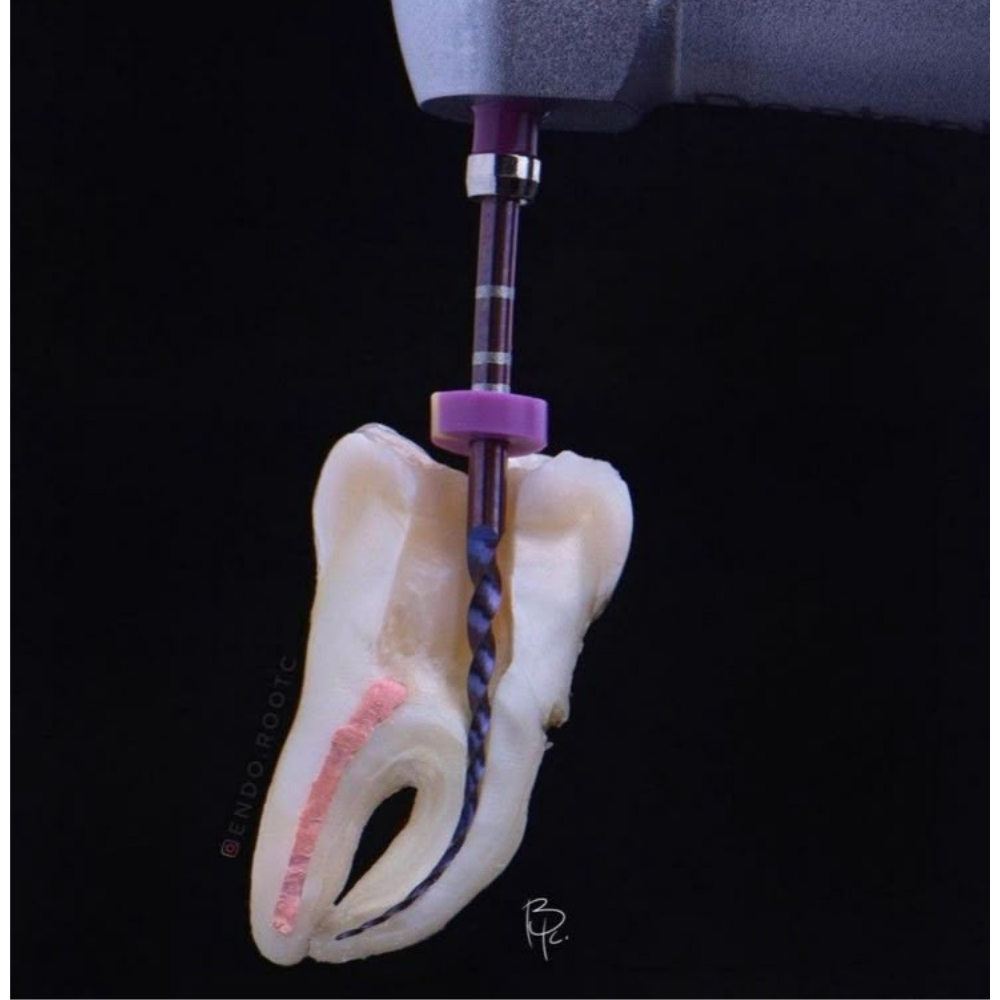

La endodoncia es la especialidad odontológica encargada de tratar el interior del diente (pulpa dental) cuando está inflamado o infectado, permitiendo salvar la pieza dental y evitar su extracción.

- Eliminación del tejido pulpar dañado

- Limpieza y desinfección de los conductos

- Sellado del conducto